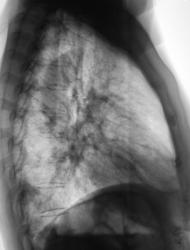

При расшифровке цифровых флюорограмм пациентка была "взята на контроль".

Произведено стандартное дообследование.

Жалоб пациент не предъявляет. Возникло сильное желание без промедлений направить пациентку на консультацию в ОКБ. Коллегиально решили провести противовоспалительную терапию, а затем "провести контроль".

После проведения противовоспалительной терапии проведен "контроль".

Ваше мнение уважаемые коллеги?

А млжет быть эти крупные очаги - метастазы?

По всей видимости, придется направить на консультацию к онкологам.